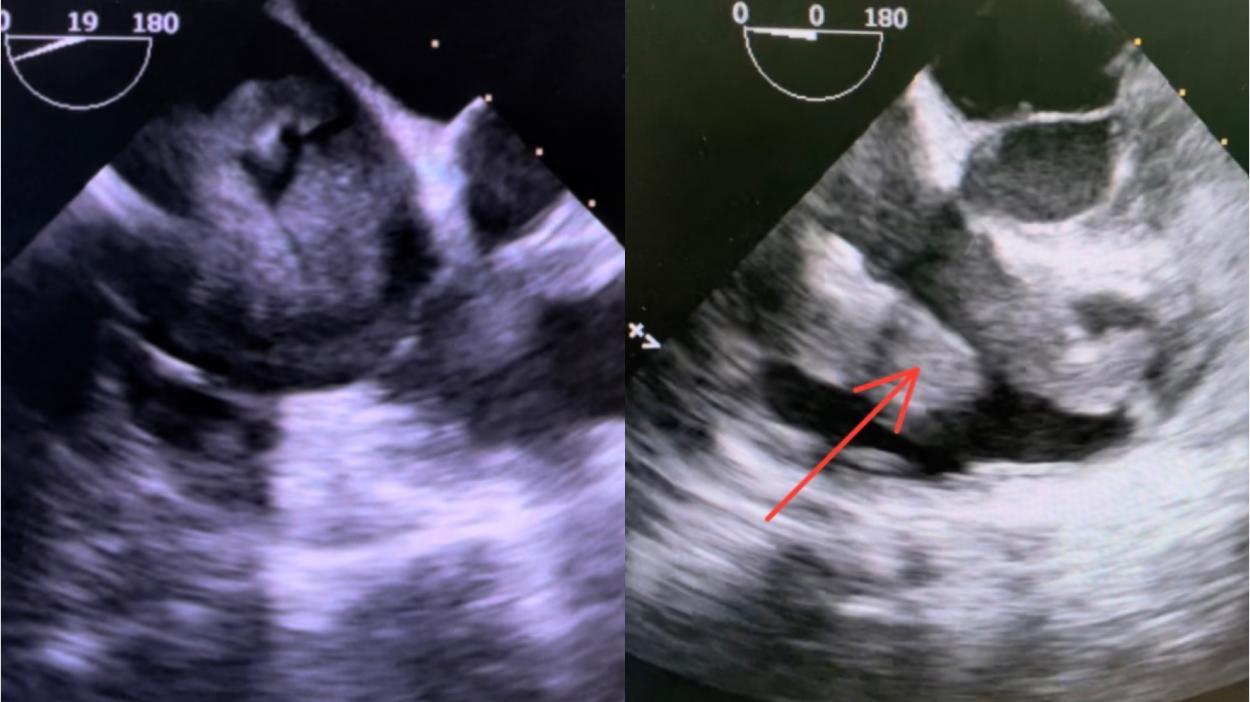

医院立即组织多学科讨论,随后心脏外科团队在征得患者及家属同意后,于6月2日联合妇科行子宫及附件全切+卵巢动静脉结扎离断+卵巢静脉内肿瘤剥脱+心内肿瘤肿瘤清除术(包括下腔静脉、右房、右室及三尖瓣瓣叶)。因术中见肿瘤已侵犯三尖瓣前后叶,遂同期行三尖瓣生物瓣置换术+心脏表面临时起搏导线植入术。术后患者心律由术前一度房室传导阻滞变为三度,考虑传导束周围组织水肿引起,遂调整临时起搏器保驾心率为70次/分,后逐渐变为窦性心律、交界性心律、II度一型交替,术后2周患者心律恢复为窦性,平均80-90次/分,经连续观察3天,患者心律稳定,病情稳定遂安排出院。

术中TEE所见